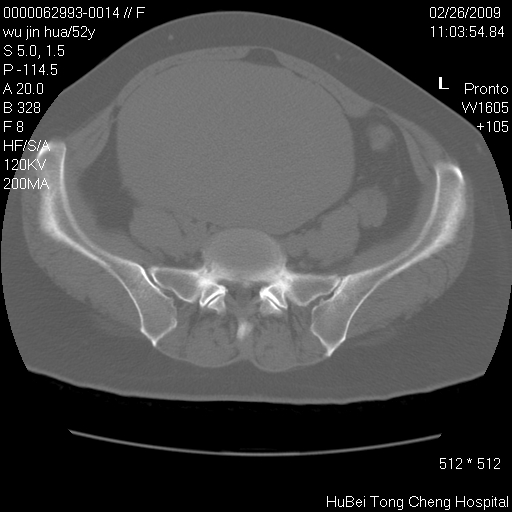

依据平片“腰椎退行性改变”报告,作椎间盘ct扫描时发现:

影像表现:盆腹腔巨大占位,内密度均匀,边界清,未做强化。